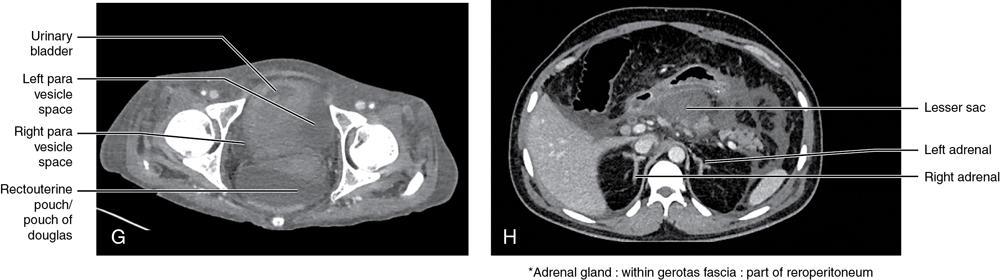

CROSS SECTIONAL ANATOMY OF ABDOMEN Satya Jha NORMAL ANATOMY OF ABDOMEN AND PELVIS Amandeep Singh The two major surfaces: The anterior and posterior layers of the coronary ligament converge on bare area (not covered by peritoneum). Its right and left margins form the right and left triangular ligaments. The right triangular ligament extends toward the diaphragm and separates right subphrenic space from right subhepatic space. The left triangular ligament gives tracts extending to the diaphragm and falciform ligament and does not compartmentalize the left subphrenic space. Ligamentum teres or the obliterated umblical vein is contained in falciform ligament which attaches the liver to anterior abdominal wall. The main portal vein, the proper hepatic artery and the common bile duct are contained within investing peritoneal folds of hepatoduodenal ligament at the porta hepatis (Fig. 7.2.2.1). Liver is divided into eight segments which are functionally independent and have their own vascular supply and biliary drainage. Arterial circulation: The branches of the hepatic artery accompanying the portal veins. Hepatic venous system: The right, middle, and left hepatic veins draining into IVC (Figs. 7.2.2.2 and 7.2.2.3). The gallbladder is a blind pear-shaped muscular membranous sac which is an embryologic derivative of the foregut, is a pouch lying along the undersurface of the liver. The gallbladder fossa is located in the plane of the interlobar fissure, which lies between the right and left hepatic lobes. Its major function is to store and concentrate bile which is produced by the liver. It measures approximately 4 cm in diameter when it is normally distended. Gallbladder is a smaller tubular structure in contracted state. The normal gallbladder wall thickness ranges from 1 to 3 mm. The gallbladder is divided into the fundus, body and neck. Infundibulum is present in the region of neck of the gallbladder, which is called the Hartmann pouch, where gallstones are usually impacted. Intrahepatic biliary radicles (IHBRs) scattered throughout the liver get confluent towards the hilum. They unite to form the right and left main hepatic ducts which further unite to form common hepatic duct (CHD) at the hilum. Common bile duct is formed by the union of cystic duct with common hepatic duct. The main pancreatic duct is joined with the common bile duct to form the ampulla of Vater at the major duodenal papilla (Figs. 7.2.2.4 and 7.2.2.5). Pancreas is located in anterior pararenal space of retroperitoneum anterior to perirenal (Gerota’s) fascia and posterior to parietal peritoneum. It is divided into head, uncinate process, neck, body and tail from right to left. Pancreas lies anterior to portal vein, which marks the point of transition between the body and neck. The region between head of pancreas and second and third parts of duodenum is known as the pancreatic groove. In postnephrectomy cases or with agenesis of kidney or ectopic kidney, pancreas moves posteriorly to partially fill in the empty renal fossa; its soft tissue density should not be mistaken for recurrent tumour. It is located in the pancreatic groove and is bounded superiorly by the duodenal bulb, laterally by second portion of duodenum, inferiorly by third portion of duodenum, medially by superior mesenteric vein and anterior to inferior vena cava. It is a wedge or wedge shaped lying posterior to superior mesenteric artery and vein. It is an imaginary junction between the head and body and lies directly over the junction of the splenic vein and superior mesenteric vein. It is located posterior to the lesser sac and anterior to the aorta, left adrenal gland, left kidney, and renal vessels and runs obliquely upward to the left of the superior mesenteric vessels. It is situated median to the colonic flexure and anterior to the left kidney. It is located in close proximity to the splenic hilum without a notable relation with the body of pancreas. It is seen anterior to the left kidney and median to the colonic flexure. The distal part of the tail passes between the peritoneal layers of the splenorenal ligament (Fig. 7.2.2.6 and 7.2.2.7).